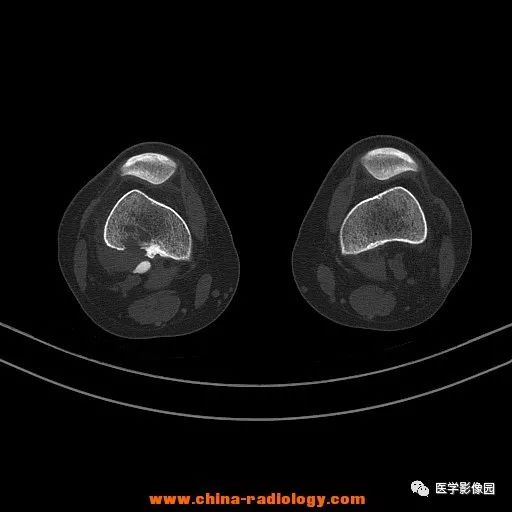

患者女性,29岁,右膝关节痛疼3月余,局部无红肿。

影像学表现:右股骨远端外后方可见局限性骨质破坏及软组织肿块,边界清楚。

病理结果:梭形细胞瘤